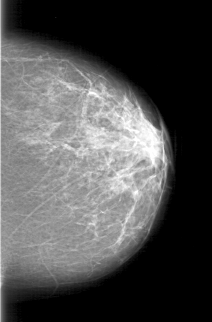

D_4197_1.RIGHT_CC

LEFT_CC LINES 5461 PIXELS_PER_LINE 3601 BITS_PER_PIXEL 12 RESOLUTION 43.5 NON_OVERLAY